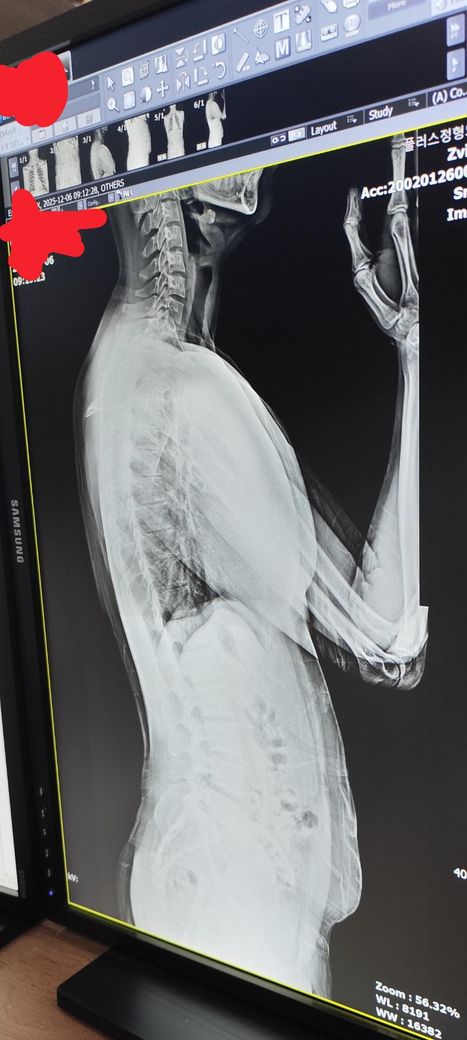

거북목인가요? (엑스레이 첨부).

거북목, 일자목인가요? 신경과에서는 일자목이라고하고 정형외과에서는 정상이라고 해서요.. 엑스레이 보시고 판단해주시면 감사하겠습니다.

엑스레이만 기준으로 설명드리면, 목뼈의 정상적인 C자 커브(경추 전만)는 개인차가 있지만 어느 정도 부드러운 굴곡이 보이는 것이 일반적입니다.

지금 사진에서는

• 경추 전만이 조금 덜 보이는 편(완전한 역C자까지는 아님)

• 즉, 가벼운 일자목에 가까운 형태로 보이긴 합니다.

• 다만 구조적 이상(탈구, 골절, 디스크 간격의 급격한 감소 등)은 특별히 뚜렷하게 보이지 않습니다.

• 자세·근육 긴장으로도 이런 형태가 쉽게 나옵니다.

따라서 전문과 의견이 갈릴 수 있는 수준이며, 엄밀히 병적 거북목이라기보다는 경추 만곡이 약해진 경향 정도로 보는 것이 일반적인 판단입니다.

증상(통증, 결림, 두통, 팔 저림)이 없다면 큰 문제로 보긴 어렵고, 증상이 있다면 자세교정·경추 안정화 운동·근긴장 관리가 도움이 됩니다.

X-ray만 보면 “목의 생리적 C커브가 다소 곧아져 보이는 편이라 ‘경추 일자목(정렬 감소)’ 소견에 더 가깝습니다.“

다만 ”심한 거북목(앞으로 돌출된 머리 자세)“ 정도는 크지 않아 보이고, 기능적 자세 문제로도 이렇게 나올 수 있습니다.

경추부위 엑스레이 사진상 완만한 만곡이 형성되어 있는것이 정상이지만 작성자님의경우 비교적 일자인 것으로 보입니다

x-ray 검사 사진을 옆에서 찍어 정확히는 알 수 없으나 일자목은 아닌 것으로 보이며 거북목을 확인하기에는 외이도 부분이 사진상 보이지 않아 정확히 알 수가 없을 것 같습니다.

우선 사진 한장만으론 판단을 하긴 어렵지만 정상적인 목 커브보다는 약간 커브 각도가 소실된것으로 보여집니다.

다만 거북목, 일자목과 같이 심한 정도는 아니기에 너무 걱정마시길 바랍니다.